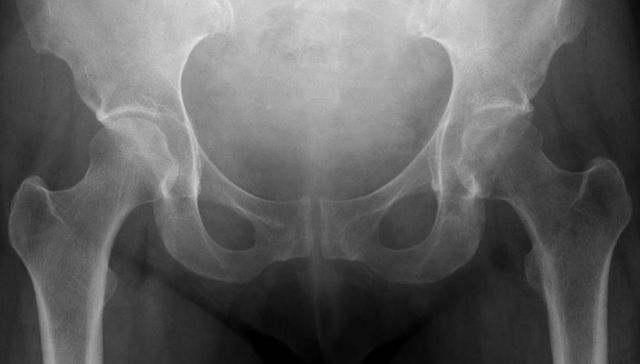

Médicos prevén que se tripliquen las fracturas por osteoporosis en los próximos 20 años